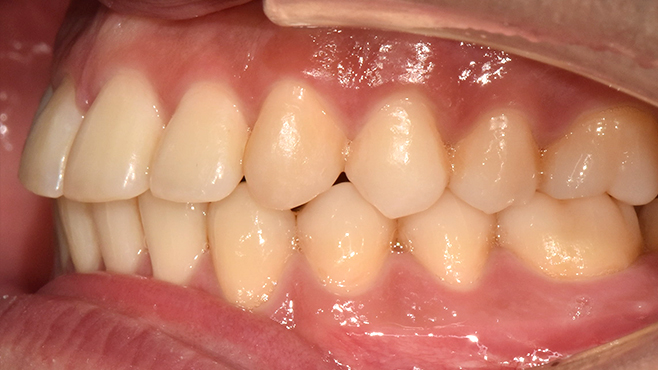

before

after

※ 위 임상사진은 동일조건으로 촬영되었으며, 사진에 대한 별도의 조작이 처리되지 않았습니다.

※ 위 임상사진 및 포트레이트는 환자와의 포괄적인 초상권 계약 이후 사용하고 있습니다.

※ 수술 및 치료과정에서 부작용이 발생할 수 있으므로 충분한 상담과 신중한 판단이 요구됩니다.

실제 치료 사례

수많은 환자들이 고민 끝에 선택한 치료,

그리고 그 후의 놀라운 변화

- ※ 위 임상사진은 365서울원탑치과에서 진료를 시작하고 마친 동일한 환자의 사진입니다.

- ※ 위 임상사진은 동일한 장소에서 동일한 조건으로 촬영되었으며, 사진에 대한 별도의 조작이 처리되지 않았습니다.

- ※ 수술 및 치료 과정에서 부작용이 발생할 수 있으므로 의료진과의 충분한 상담과 신중한 판단이 요구됩니다.